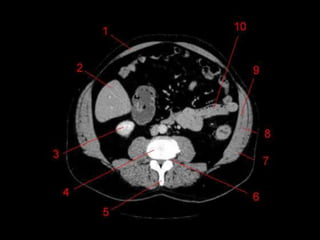

Subdivisão Funcional • Osoito segmentos são divididos: – A primeira divisão é realizada dividindo através da Porta Hepática, em esquerdo (I a IV) e direito (V a VIII) – A divisão é feita baseada em um relógio – Caudado é o segmento I – No ‘lobo’ esquerdo, o IV separa-se do II e do III pela veia hepática esquerda, representado anatomicamente pelo ligamento falciforme. – II e III se dividem através de uma linha imaginária transversal na altura da porta hepática. – No ‘lobo’ direito, se divide os segmentos através de uma linha transversal e pela veia hepática direita.

Subdivisão Funcional • Fundamentalimportância para Ressecção. • Maioria das lesões são do fígado direito.

Vesicula Biliar • Localizadona superficie visceral, entre o fígado direito e esquerdo. • 50 ml de bile. • Dividido em Fundo, Corpo, Colo e Infundíbulo. • Peritônio recobre o fundo, e aproxima o corpo e o colo ao fígado • CT: 4-5mm – Parede: 1 – 3,5 mm.

Técnicas de Imagem •Rx: – 10 – 15% das colelitiases, estão calcificadas e identificáveis no RX – Pode ser visto também a vesícula em “porcelana.” – Gás pode ser visto dentro das pedra: Sinal de Mercedes-Benz – Colecistografia oral: Ingesta de composto iodado. Atualmente susbstituído pelo US

• 44.

Técnicas de Imagem •US – Método de escolha • Colecintigrafia – Estudo dinâmico. Ver obstruções. • Colangiografia – CPRE: Diagnóstica e Terapêutica. • TC – Menos sensível que US para detectar dilatação.